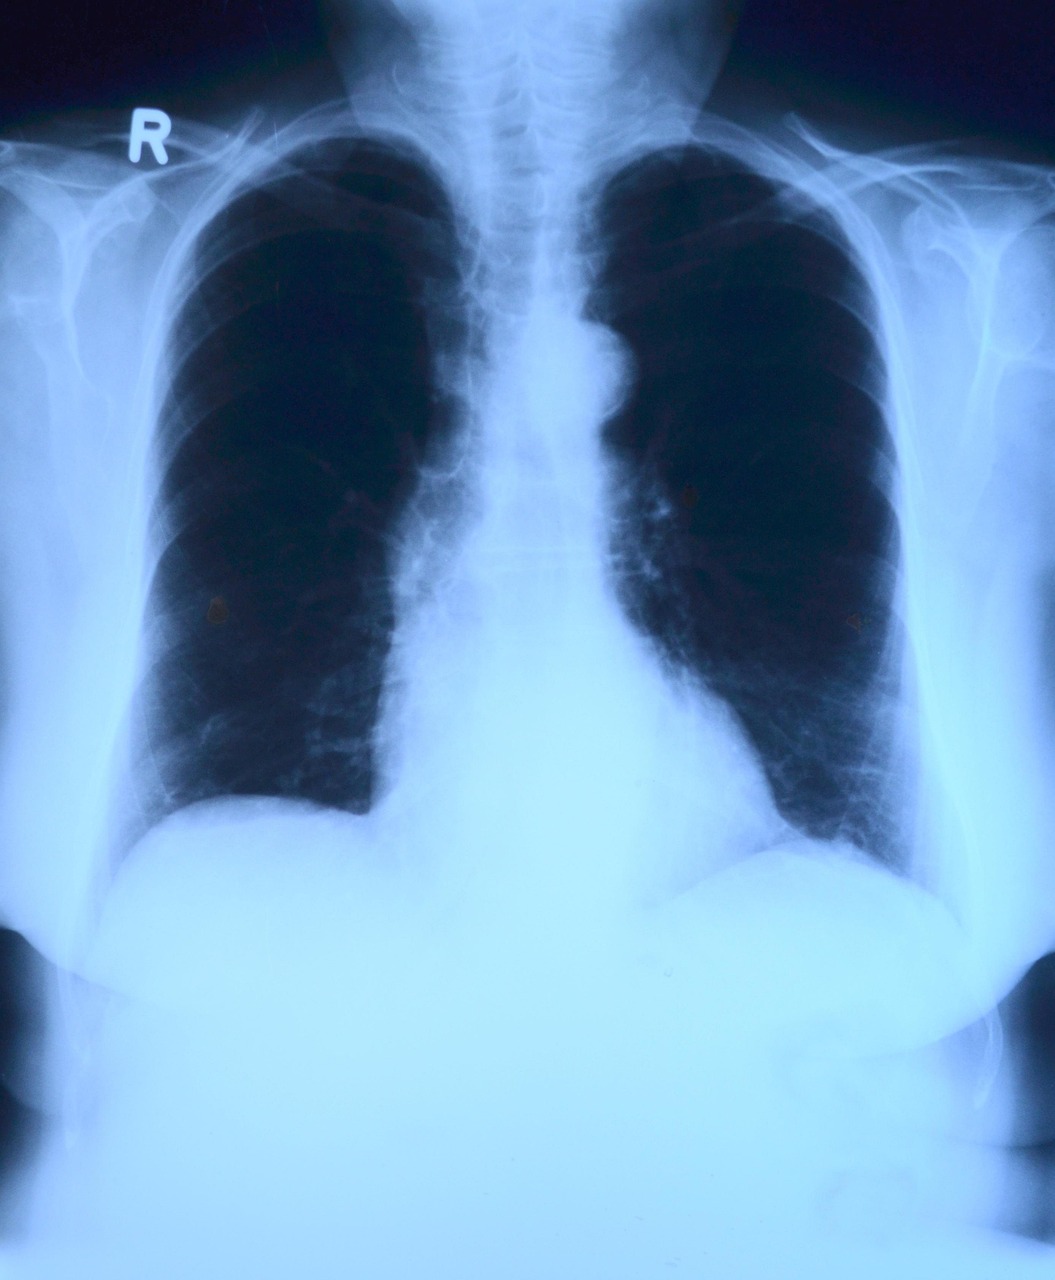

Pneumokokna bolest posebno je opasna za decu, starije od 65 godina i osobe sa hroničnim oboljenjima. Može izazvati upalu pluća, sepsu i meningitis, a invazivni oblici bolesti imaju smrtnost i do 30 odsto. Rizik je najveći kod starijih, hroničnih bolesnika, pušača i imunokompromitovanih pacijenata.